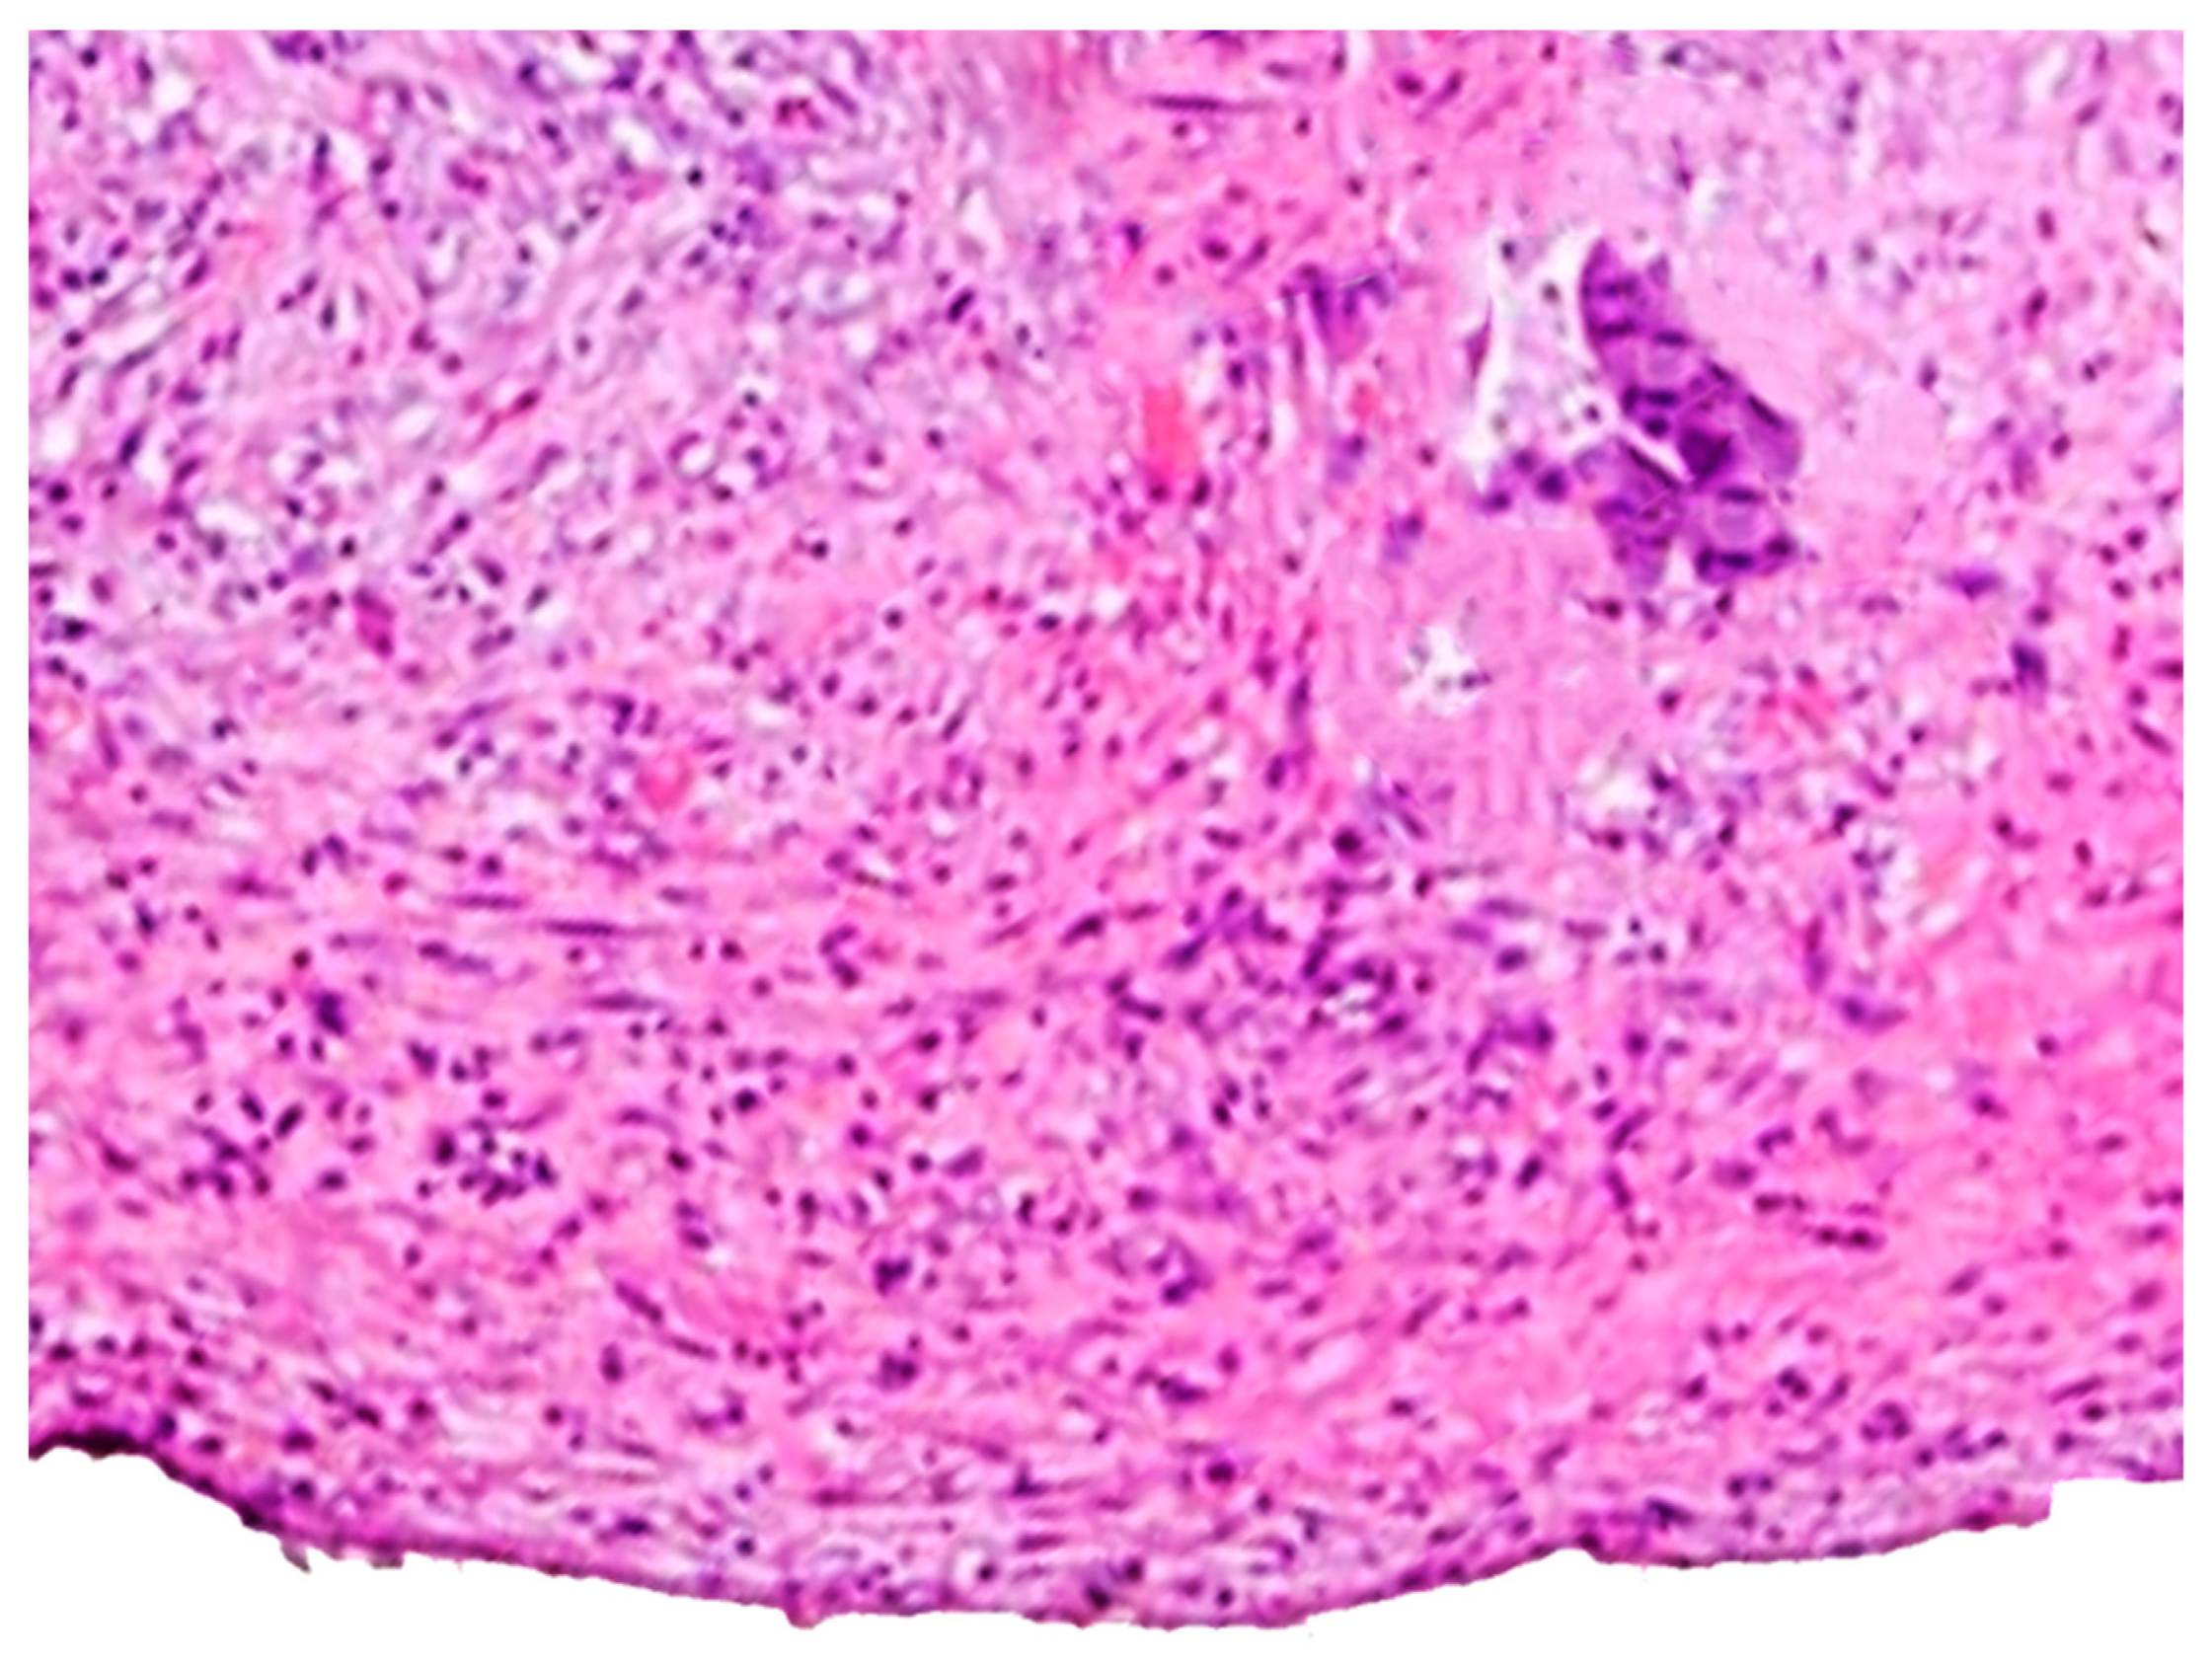

Identification of an Objective Cut-Off Point to Define the Clinical Stage T4a in Colon Cancer

- Zwanenburg, E.S.; Wisselink, D.D.; Klaver, C.E.; van der Bilt, J.D.; Tanis, P.J.; Snaebjornsson, P.; Andeweg, C.S.; Bastiaenen, V.P.; Bemelman, W.A.; Bloemen, J.; et al. The measured distance between tumor cells and the peritoneal surface predicts the risk of peritoneal metastases and offers an objective means to differentiate between pT3 and pT4a colon cancer. Mod. Pathol. 2022, 35, 1991–2001. [Google Scholar] [CrossRef] [PubMed]